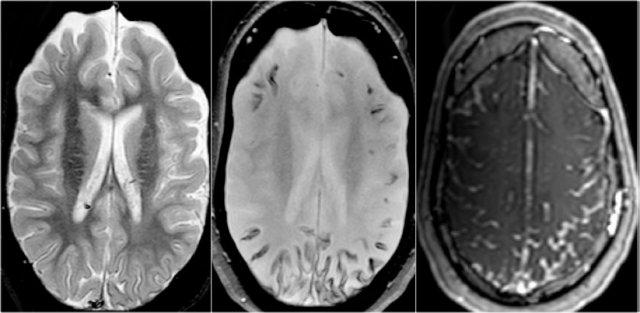

Chuỗi xung T2W và T2* gradient echo cho thấy nhiều cavernoma.

Lưu ý hình ảnh “bỏng ngô” với vành hemosiderin ngoại vi trên chuỗi xung T2W.

Các tổn thương gần như hoàn toàn màu đen trên chuỗi xung gradient echo do xảo ảnh blooming.

Chuỗi xung T2* và hình ảnh trọng số độ nhạy từ (SWI) làm tăng đáng kể độ nhạy của MRI trong việc phát hiện các cavernoma nhỏ.

Năm chấm đen ở bán cầu đại não trái trên chuỗi xung T2* cũng là cavernoma và không thể nhìn thấy trên chuỗi xung T2W.